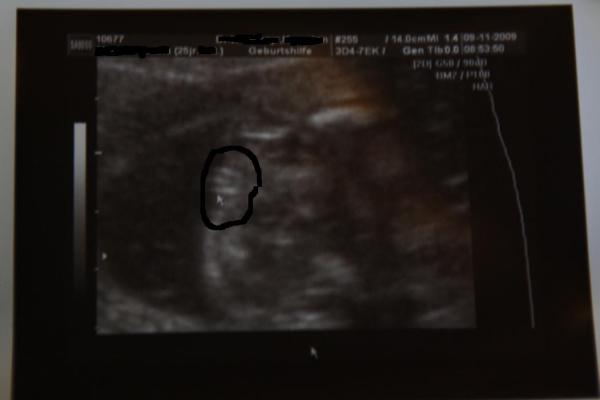

Hallo Mädels, war heut beim Doc, weil ich ja krank bin und ne Krankschreibung gebraucht hab, bzw. weil mir seit Tagen (heut leider wieder schlimmer) so mein Rücken und meine Leisten weh tun - sind wohl die Bänder in der Wirbelsäule vom vielen Husten... Er hat auch geschaut, ob mein Muttermund auch bei kräftigem Husten fest zu ist - ja ist er, bin sehr froh. Und dann hat er gefragt, ob wir nochmal schauen sollen, obs noch ein Mädel ist... und was soll ich sagen ------ JAAAAAAA ES IST UND BLEIBT EIN MÄDCHEN Und ich hab sogar ein Beweisfoto mitbekommen, das ich euch natürlich nicht vorenthalten will... Am Montag hab ich wieder VU, dann gibts die Daten dazu!! vlg Manu

Bild zu Außerplanmässig beim Doc + 100% Outing (mit Foto)! - Forum für März - Mamis

Klasse...so ähnlich (nur mit feineren Linien) sah mein Beweisbild (bei 17+2) auch aus;-)))) HERZLICHEN GLÜCKWUNSCH Liebe Grüße Swantje, die ab heute in der 23.SSW ist

Herzlichen Glückwunsch zur kleinen Prinzessin! Das ist eindeutig ein Mädel!